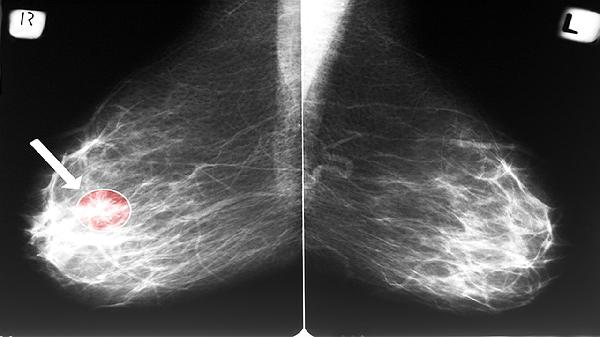

恶性肿瘤细胞通常表现出更显著的核异常。核质比失调、核轮廓不规则、染色质呈粗颗粒状分布是典型特征。例如鳞状细胞癌可见核仁突出,腺癌可能出现核分裂象活跃。某些血液系统肿瘤如淋巴瘤,细胞核可能出现切迹或分叶状改变。但最终诊断需依赖免疫组化标记、分子检测等辅助检查。